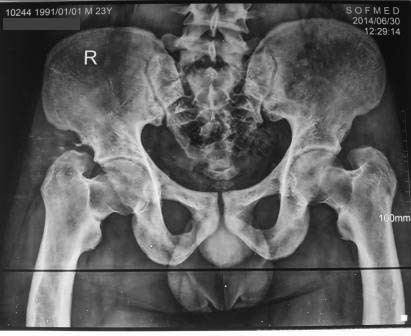

Уважаемые коллеги! Обратился пациент 23г. Оказалось в 1998г оперирован у меня по поводу болезни Блаунта, методом Шаргородского.

( Болезнь семейная, оперированы мать, тетя, дядя и др. родственники.)Беспокоить боли, ограничение и чувство нестабильности в обеих т/б суставах, скованность, особенно утренная.

Пока конкретного мнения нет, может быть межвертельная вальгизирующая остеотомия?

Уважаемые коллеги, помогите советом, что рекомендуете в данном случае.

Фото и р-снимки прилагаются.